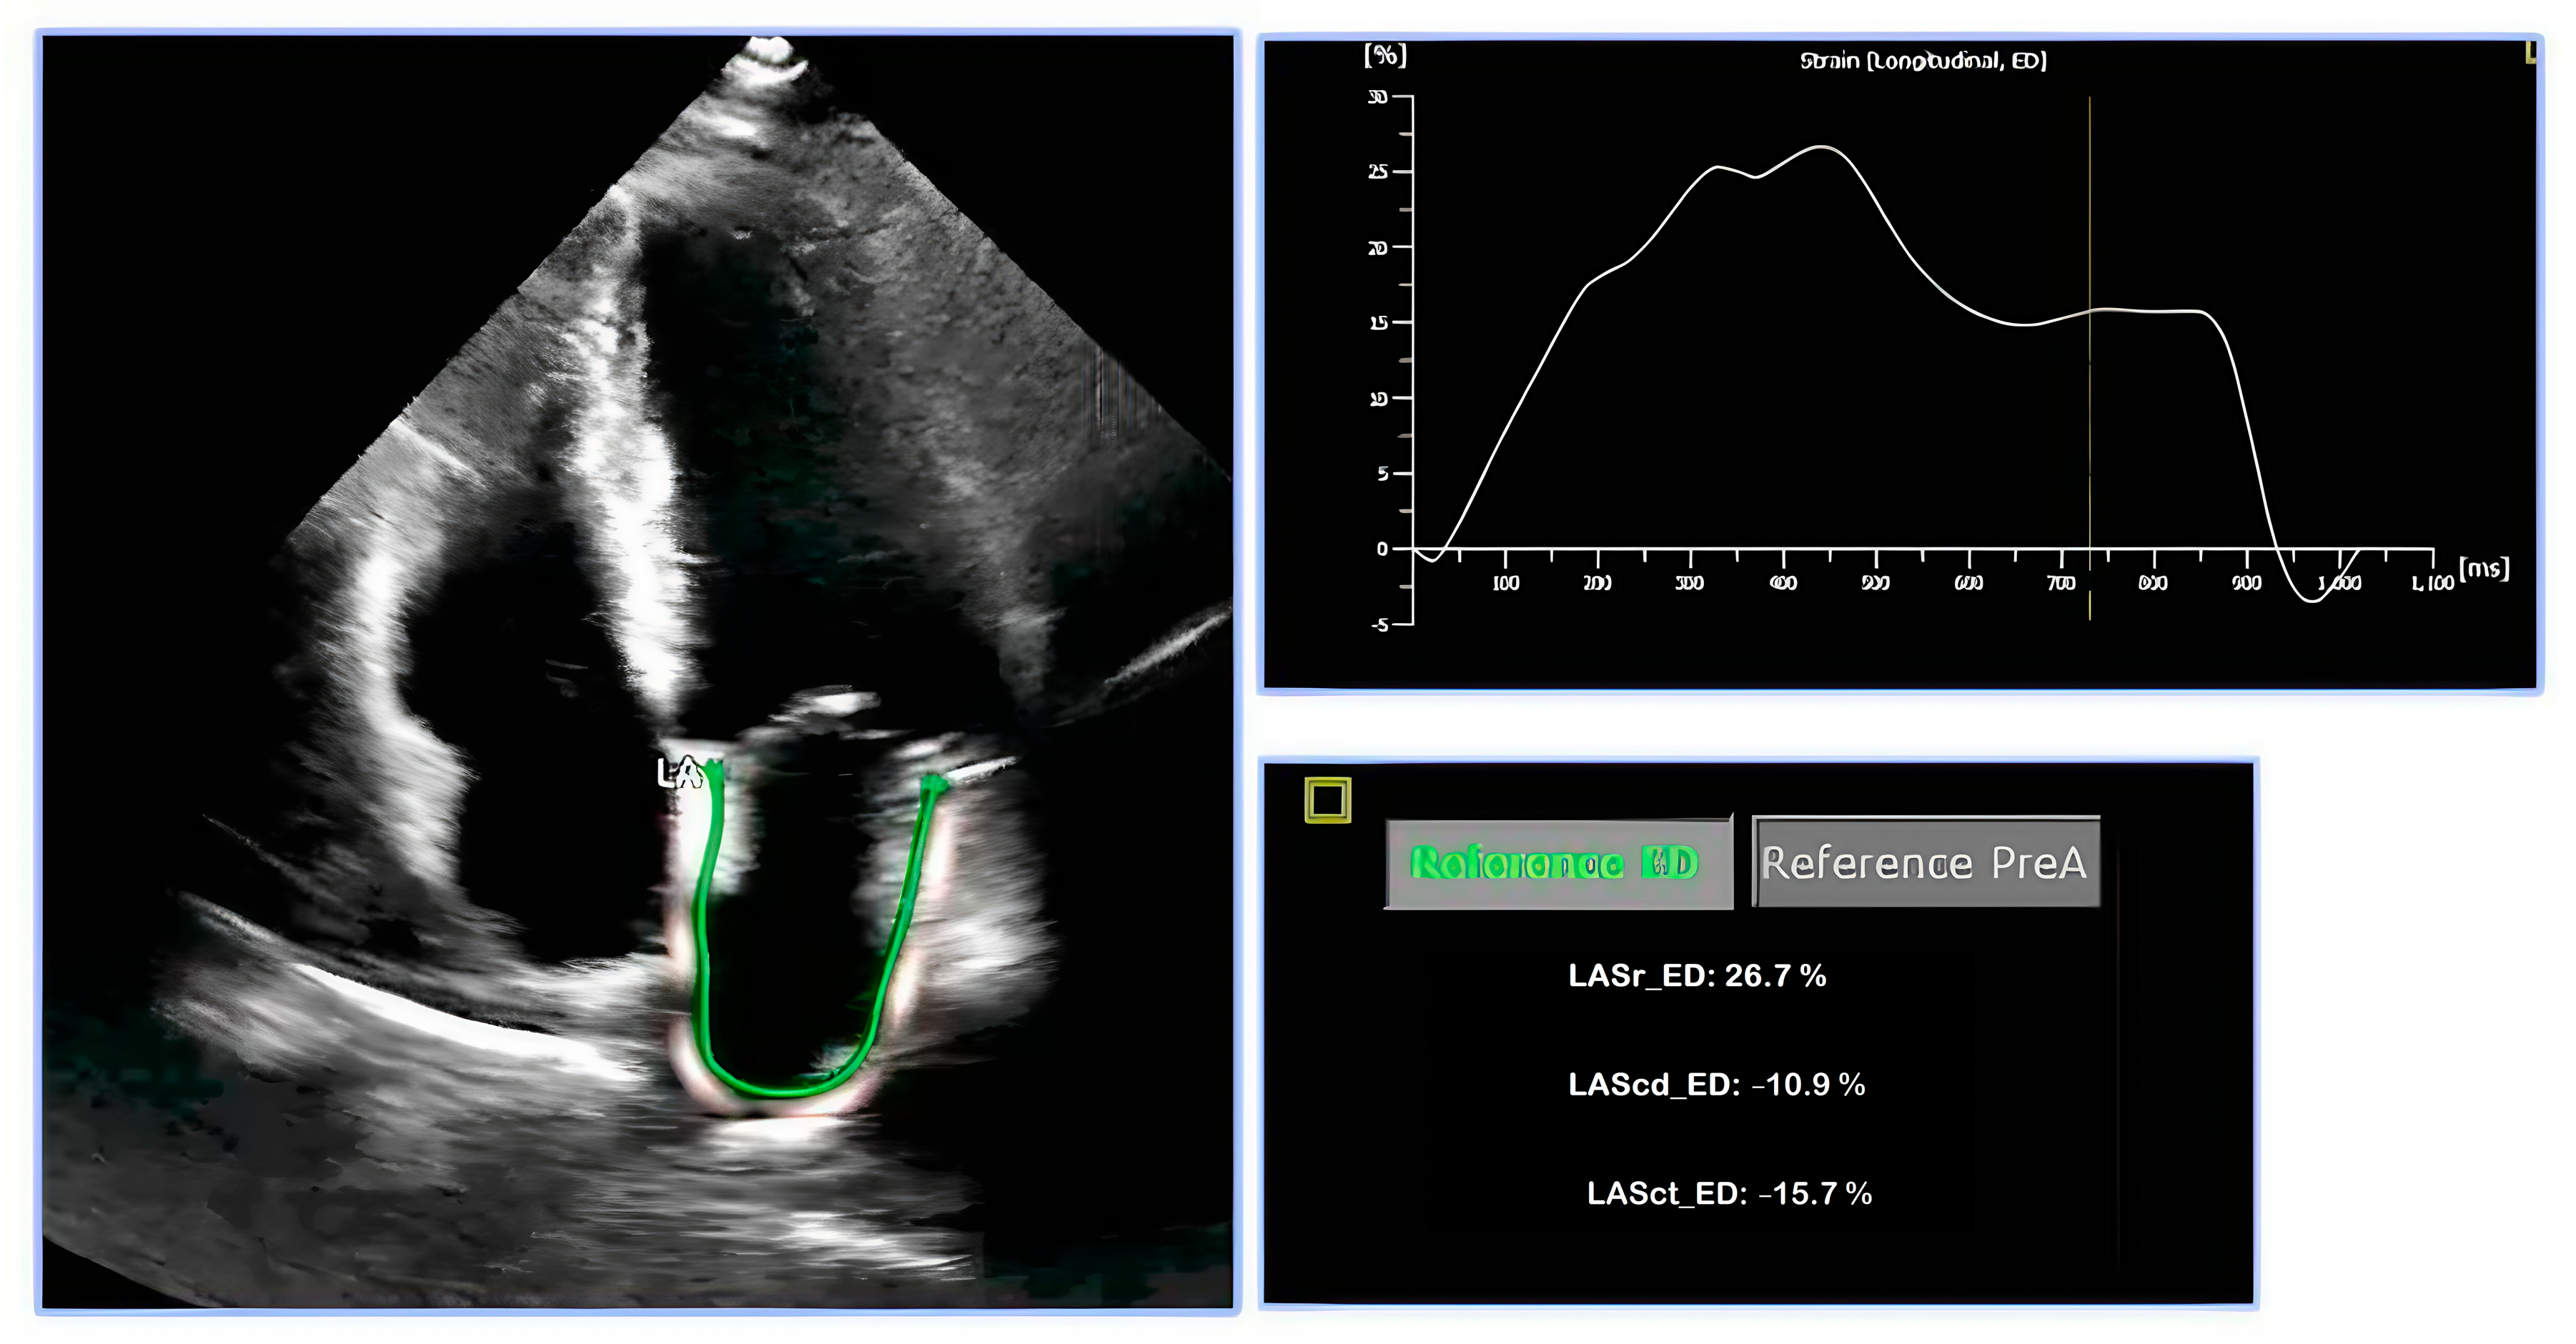

2. Assessment of LA Strain

2.1. Speckle-Tracking Echocardiography